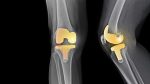

Αρθροπλαστική γόνατος. Η αντικατάσταση της άρθρωσης του γόνατος όταν έχουν καταστραφεί οι φορτιζόμενες επιφάνειές του Η αρθροπλαστική γόνατος είναι μια χειρουργική επέμβαση κατά την οποία οι φθαρμένες φορτιζόμενες επιφάνειες του γόνατος αντικαθίστανται με τεχνητά υλικά. Ο κατεστραμμένος αρθρικός χόνδρος του μηρού και της κνήμης αφαιρούνται και στη θέση τους τοποθετούνται μεταλλικά ενθέματα τα οποία είναι, … Συνεχίστε να διαβάζετε το Αρθροπλαστική γόνατος.